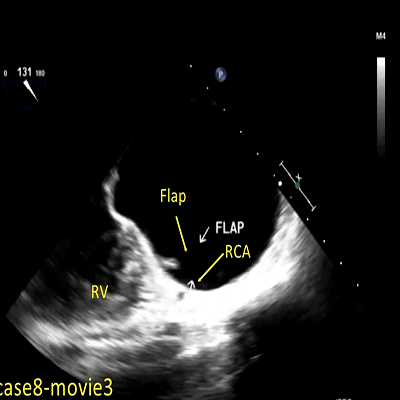

Aortic dissection flap

1 MB